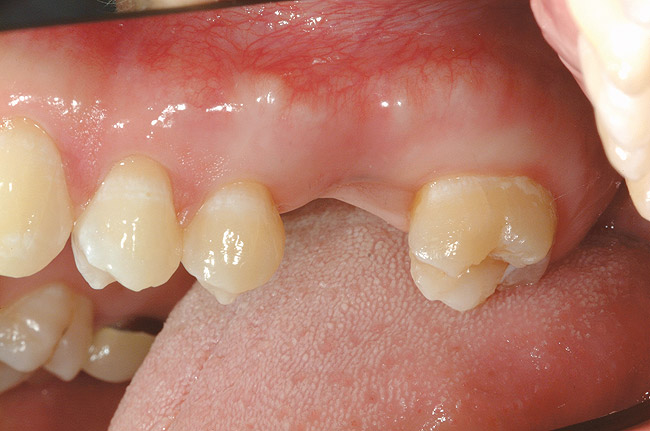

Figure 1  Replacement of a missing tooth has long been a treatment objective to improve oral health and function.

Figure 1

Tooth replacement has long been an established treatment objective to provide proper function and oral health. This is evident in the educational process that dental students receive early in their predoctoral training1-5 (Figure 1). However, much debate remains as to the best treatment alternative. Most dentists have been taught that a fixed prosthodontic option is the first choice and is preferable to a removable partial denture (RPD). This viewpoint can be readily observed from the disproportionate number of fixed prosthodontic restorations, compared with RPDs, being fabricated by the dental laboratory technicians. Yet the long-term prognosis for these treatment modalities should be questioned, especially because both types are dependent on abutment teeth for retention and support of the prostheses.2,4 Recurrent decay remains the primary cause of failure for both fixed and removable prostheses, followed by loss of one or more abutment teeth. This may make future restorations using the same type of prostheses difficult, if not impossible. Today, dental implants provide dentists with an alternative for tooth replacement.